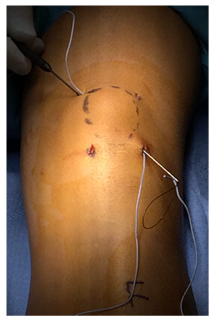

We report a case of a 15 year old female who sustained a left side transverse distal patella fracture (Figure 1) while participating in tack and field upon landing after long-jump.  After a thorough discussion of non-operative verses operative treatment, the patient and her parents elected to move forward with fixation of the fracture to promote healing, allow early mobilization and minimize the risk of displacement. Because of minimal displacement, it was elected to move forward with a previously described suture tension band technique using #5 FiberWire.10 The unique aspect of this case is the percutaneous placement of this figure-of-8, tension band suture fixation (Figure 2).

Figure 1 Lateral radiograph demonstrating distal transverse patella fracture.